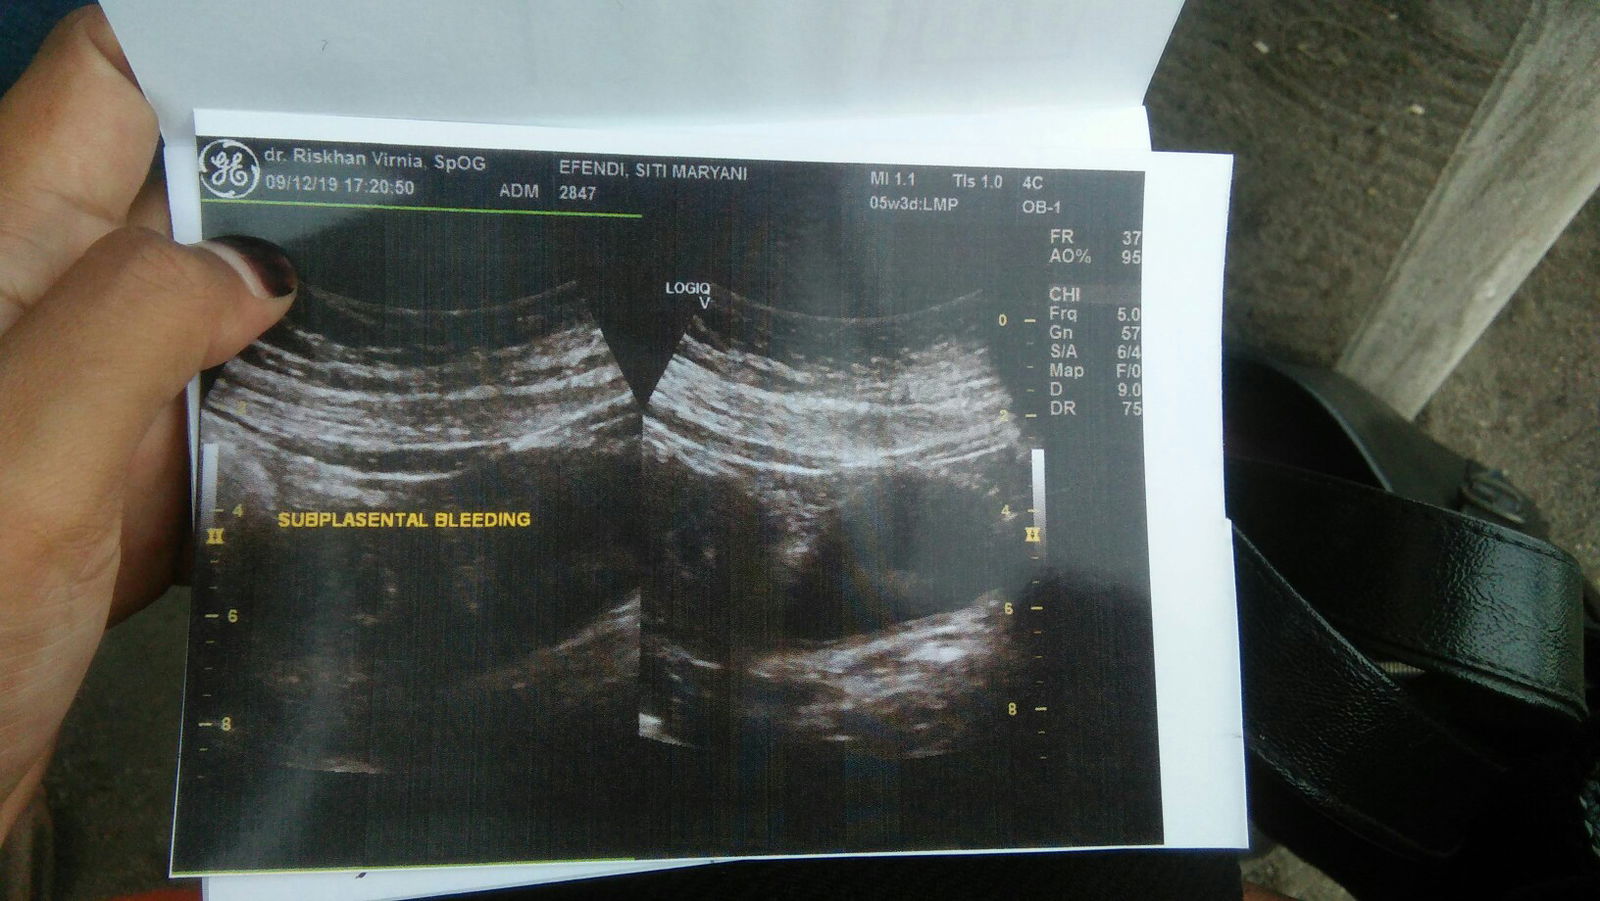

Waktu pertama tau bahwa aku hamil ya rasanya bahagia banget, karna setelah 5bulan pernikahan Allah memberikan kepercayaan.. ? Udah 5minggu usia kehamilan ku, suatu hari ada keluar flek kayak darah haid tapi gada rasa nyeri sedikit pun diperut cuma keluar sekali saja setelah itu 2hari selanjutnya keluar lagi flek jadi aku gelisah terus aku pergi usg didokter alhamdulilah kata dokter janin ku tidak apa2 cuma plasenta nya ada tergores sedikit makanya mengeluarkan darah.. ? Itu hasil usg nya ??